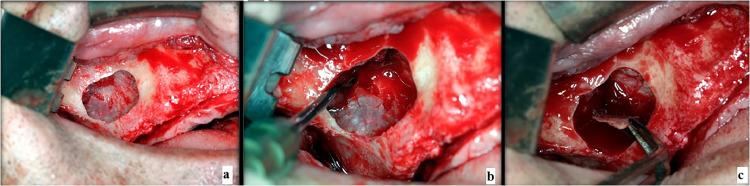

MATERIALS AND METHODS

A retrospective cohort study conducted at a single medical centre. Individuals who underwent maxillary sinus floor augmentation for dental implant placement via the lateral approach. Preoperative imaging was evaluated for anatomical variables, including the presence of septa, alveolar antral artery, Schneiderian membrane thickness, maxillary sinus lateral wall thickness, residual alveolar bone height, and maxillary sinus shape. Univariate and multivariable analyses assessed the associations between anatomical factors and EIF. A P value <.05 was considered significant.

材料与方法

在单一医疗中心进行一项回顾性队列研究。纳入通过外侧入路进行上颌窦底提升以植入牙种植体的个体。对术前影像进行解剖学变量评估,包括间隔的存在、牙槽窦动脉、施奈德膜厚度、上颌窦外侧壁厚度、剩余牙槽骨高度以及上颌窦形状。单因素和多因素分析评估解剖学因素与EIF之间的关联。P值<0.05被认为具有统计学意义。